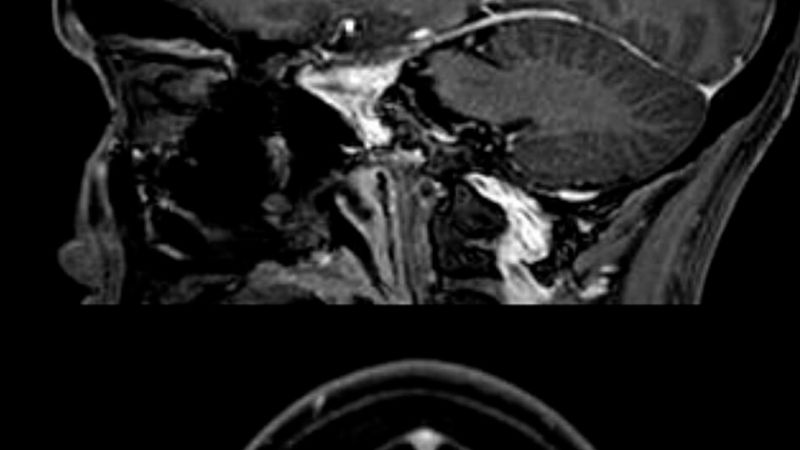

This News Anchor Was Diagnosed With Brain Cancer